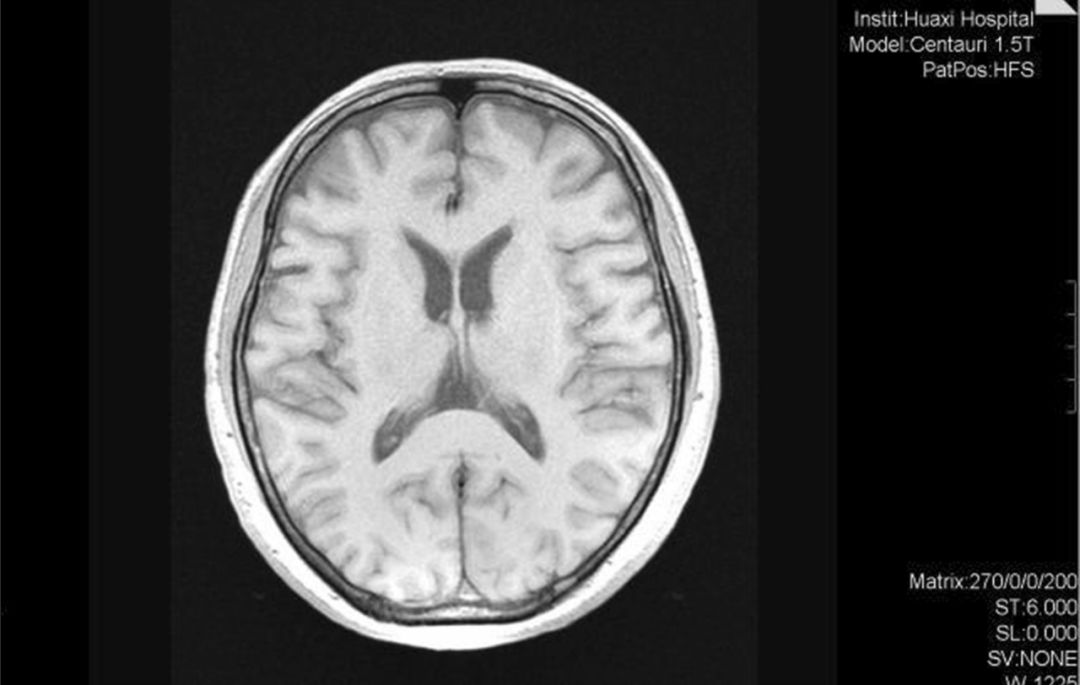

图1 2016年头部MRI未见明显结构异常(Li X, et al. 2020)

上述情况持续了大约1年后,患者被家人带至我中心门诊就诊。头部磁共振检查未发现明显的大脑结构异常(图1)。根据《精神疾病诊断与统计手册》第五版(DSM-5),患者被诊断为精神分裂症。予以奥氮平